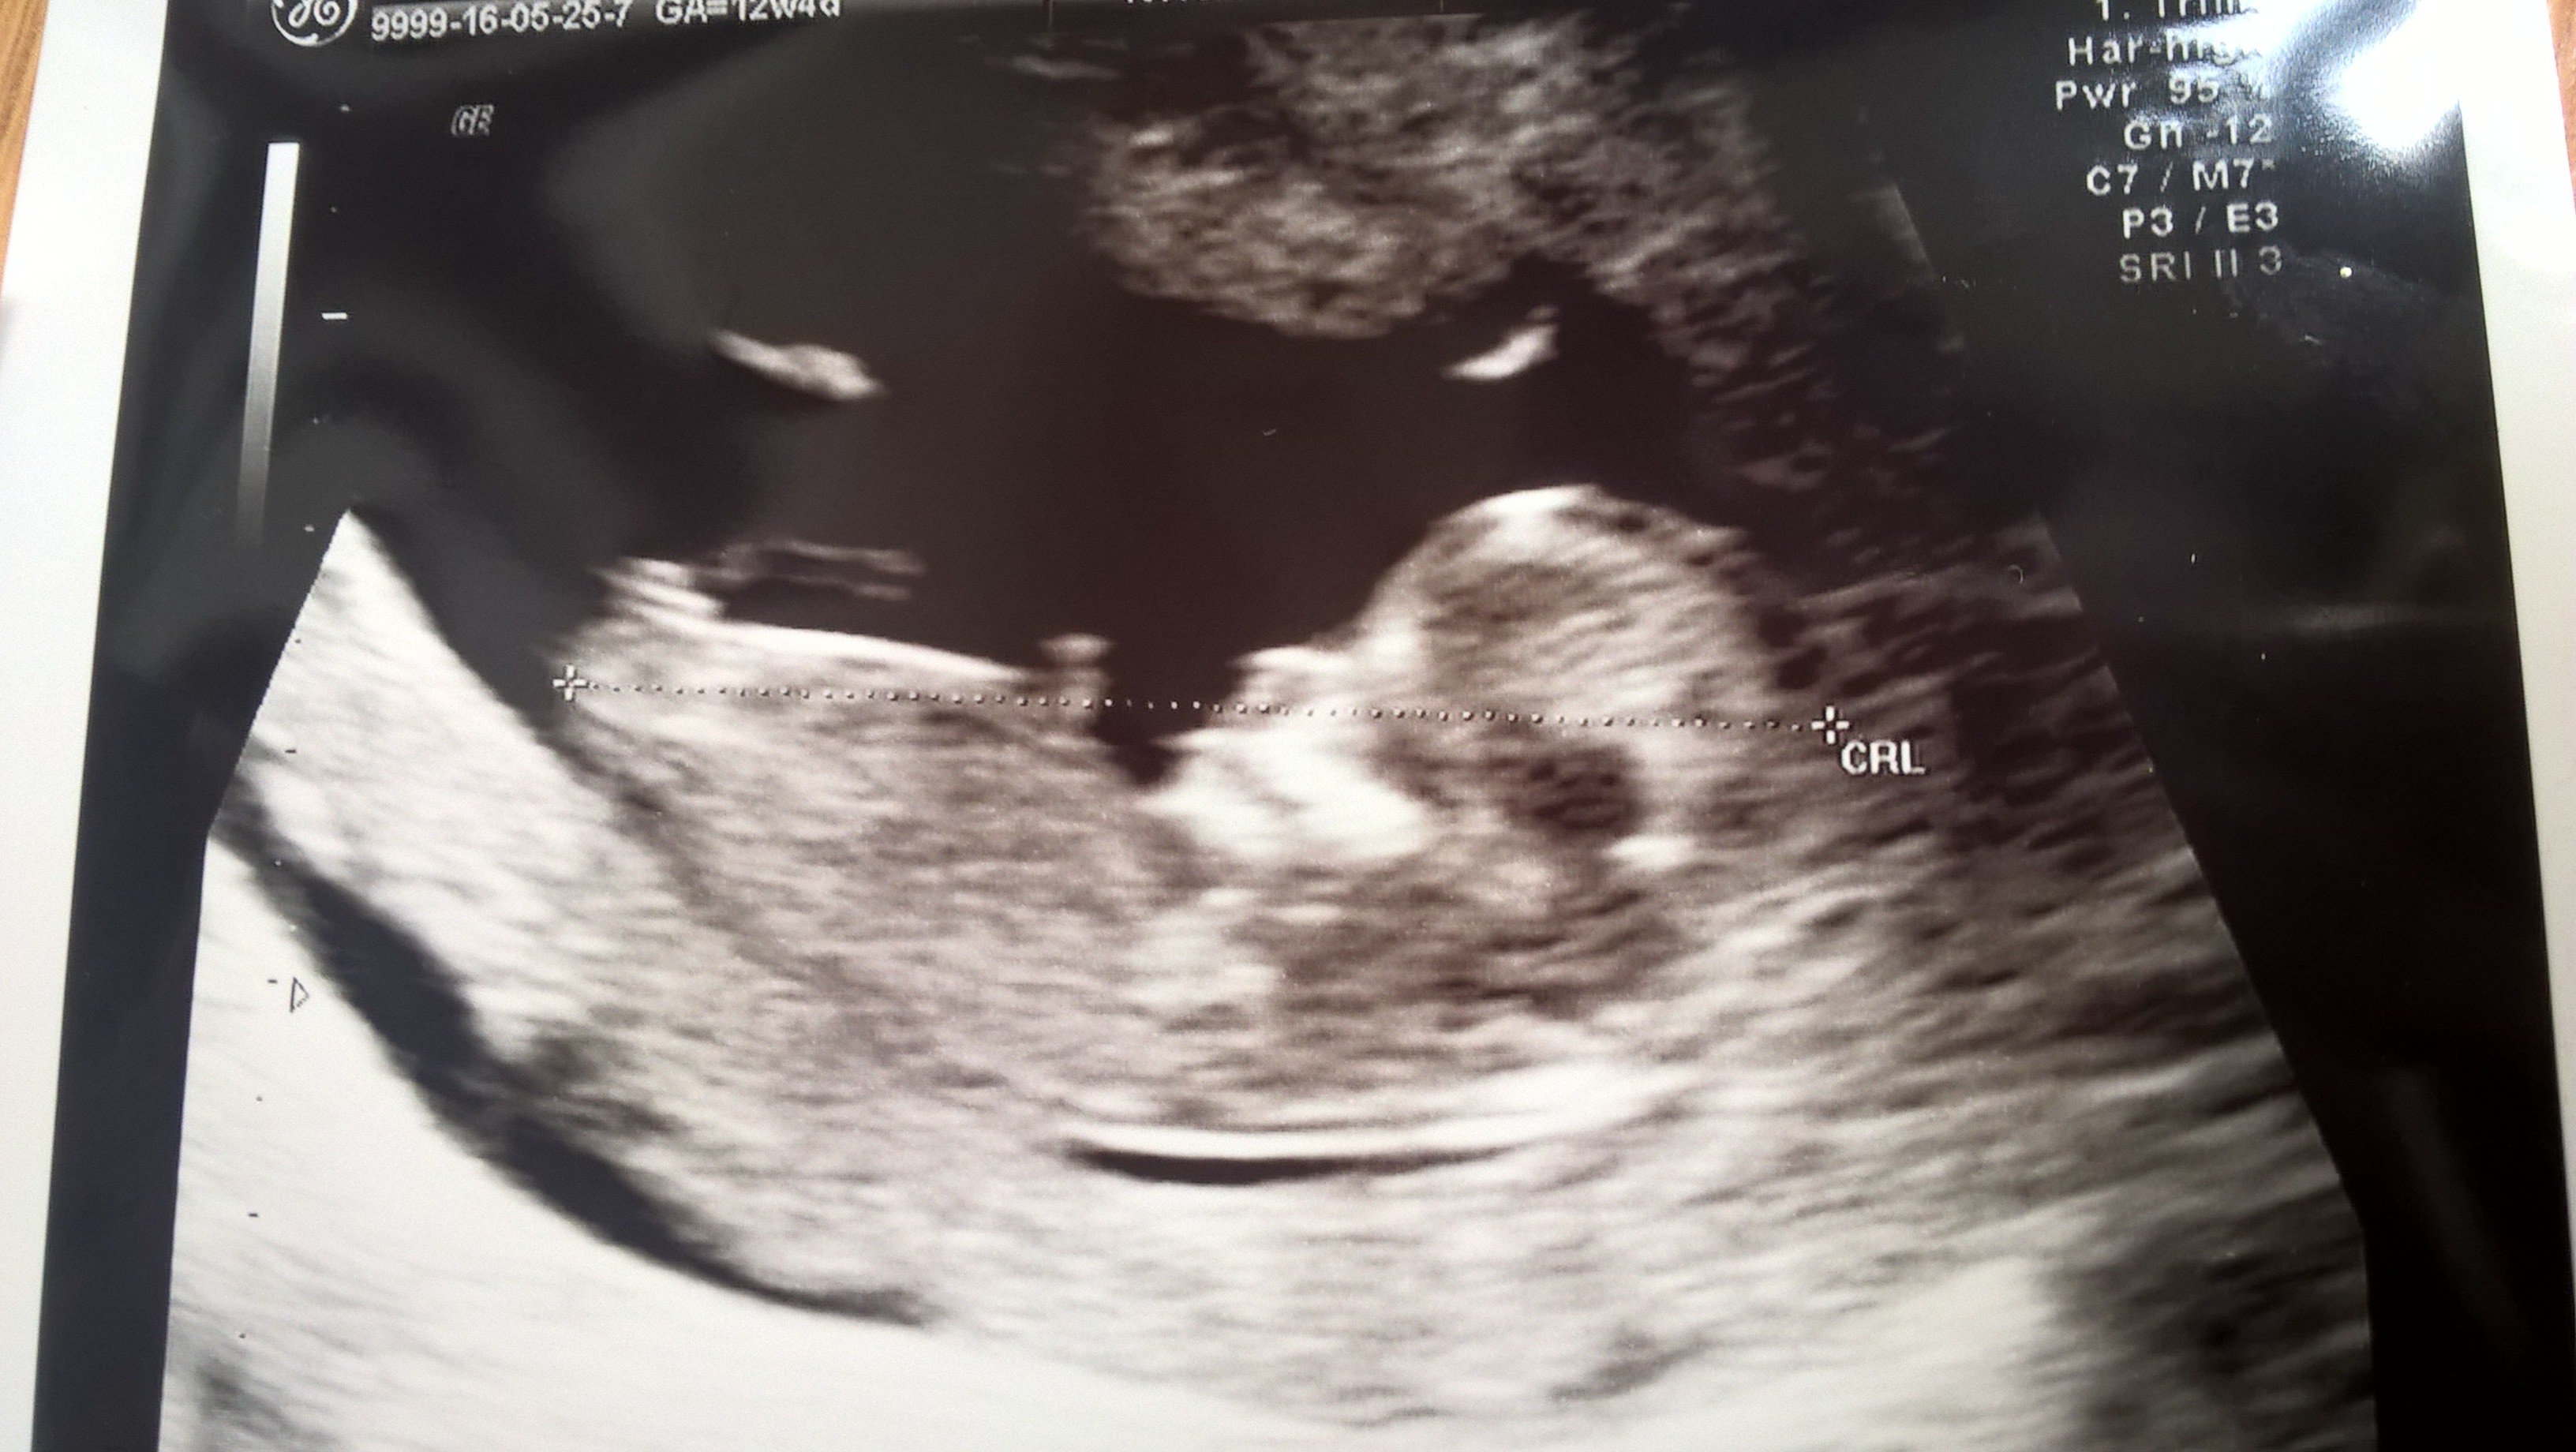

Grudnióweczki u lekarza

Kindzia możesz mi powrozyc z nuba bo ja nie kumam tego:) Zobacz załącznik 760625

Ja tu dziewczynkę widzę

Dziewczyny, a tutaj w ogóle coś widać, :D próbowałam wypatrzyć tego nuba, ale chyb coś mi nie wyszło...Zobacz załącznik 760628

Chłopiec jak dla mnie